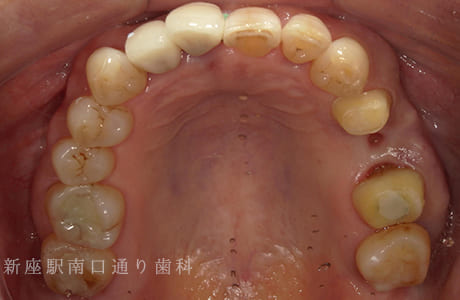

CASE.02

左上のフルジルコニアブリッジで

修復した症例

- 主訴

- 歯がないところを治したい

- 治療法

- 左上にフルジルコニアブリッジで修復

- 治療期間

- 1ヶ月半

- 費用

- ¥240,000(税込)

【リスク・副作用】

過度の咬合や衝撃で割れることがあります。治療直後は歯や歯茎に一時的な違和感や痛みが出ることがあります。